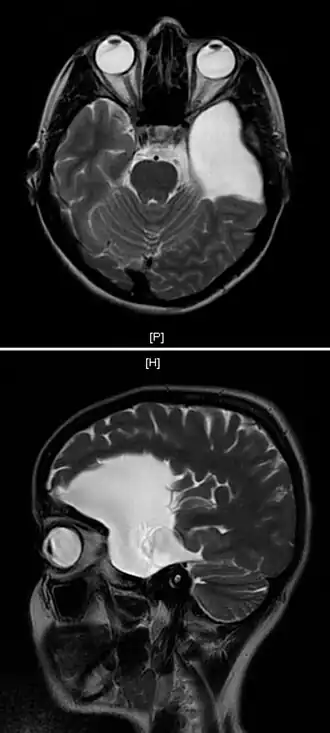

IRM du crâne d'une jeune femme de vingt-cinq ans présentant un kyste arachnoïdien fronto-temporal gauche.